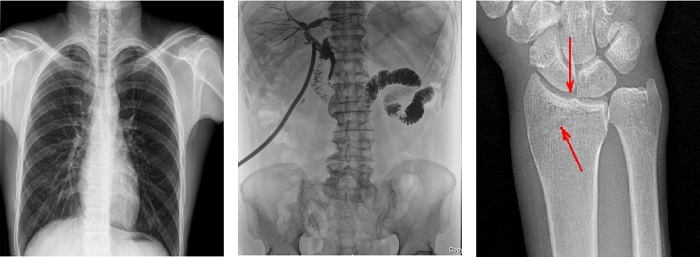

搭載100μm高品質(zhì)動(dòng)態(tài)平板探測(cè)器的普利德多功能懸吊動(dòng)態(tài)DR,不僅滿(mǎn)足常規(guī)的數(shù)字化X線全身攝影需求,同時(shí)還擁有數(shù)字?jǐn)z影、數(shù)字透視、數(shù)字造影、全景拼接等多種功能,極大地拓展了X線檢查在臨床應(yīng)用范圍,為醫(yī)院臨床應(yīng)用帶來(lái)更多實(shí)用價(jià)值?;诎傥⑵桨宓母咔宄上?,圖像清晰度與分辨率更高,可滿(mǎn)足不同檢查部位對(duì)細(xì)節(jié)成像的高品質(zhì)要求,在胸腹部、脊柱等復(fù)雜骨骼和軟組織的攝片上應(yīng)用,更便于觀察隱匿性病灶,精準(zhǔn)識(shí)別疑難病癥。

不同于靜態(tài)DR拍攝隱匿性病灶時(shí),由于組織重疊病灶難辨,耗費(fèi)時(shí)間更長(zhǎng)且易漏診、誤診,普利德多功能懸吊動(dòng)態(tài)DR可通過(guò)動(dòng)態(tài)實(shí)時(shí)連續(xù)成像,對(duì)于重疊部位病灶或者易被遮擋的病灶進(jìn)行多角度動(dòng)態(tài)觀察,毫秒級(jí)時(shí)間內(nèi)實(shí)現(xiàn)動(dòng)靜態(tài)轉(zhuǎn)換點(diǎn)片,快速、精準(zhǔn)完成攝片。比如隱匿性肋骨骨折,可在透視下觀察患者的呼、吸過(guò)程,避開(kāi)重疊影像,快速點(diǎn)片,保證檢查部位的病癥不被遺漏,實(shí)現(xiàn)精準(zhǔn)診斷。